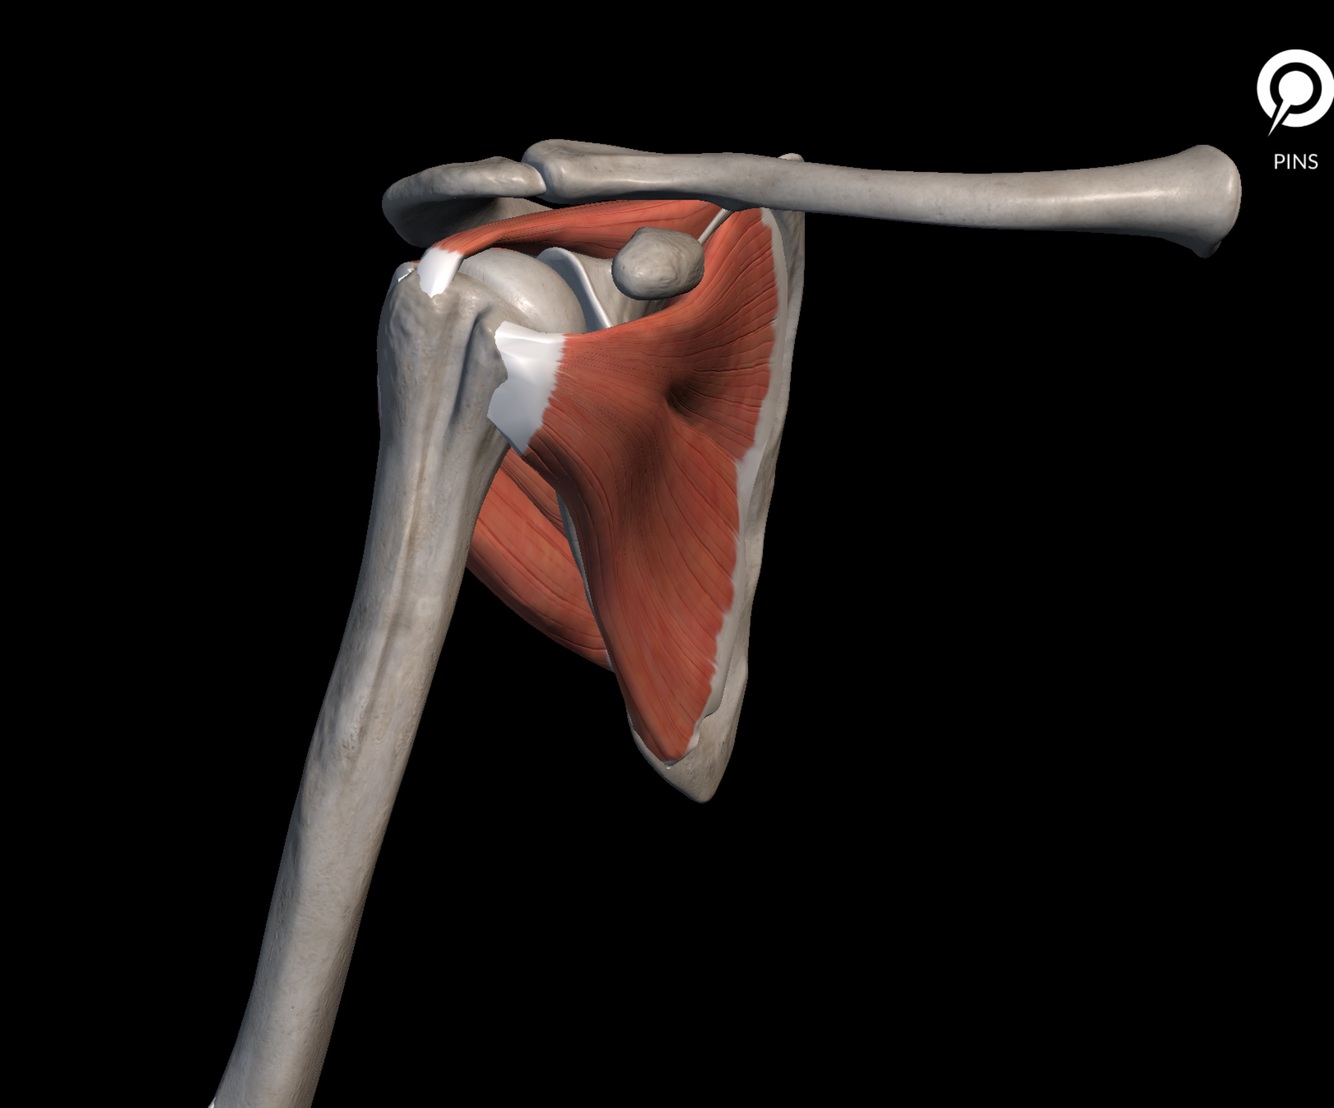

Efeito da compressão umeral em relação a glenoide é dado pelo manguito

VERDADEIRO